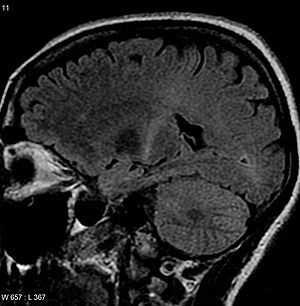

| An MRI with increased signal in the posterior part of the internal capsule that can be tracked to the motor cortex, consistent with the diagnosis of ALS | |

Because symptoms of ALS can be similar to those of a wide variety of other, more treatable diseases or disorders, appropriate tests must be conducted to exclude the possibility of other conditions.[4] One of these tests is electromyography (EMG), a special recording technique that detects electrical activity in muscles.[4] Certain EMG findings can support the diagnosis of ALS.[4] Another common test measures nerve conduction velocity (NCV).[4] Specific abnormalities in the NCV results may suggest, for example, that the person has a form of peripheral neuropathy (damage to peripheral nerves) or myopathy (muscle disease) rather than ALS. While a magnetic resonance imaging (MRI) is often normal in people with early stage ALS, it can reveal evidence of other problems that may be causing the symptoms, such as a spinal cord tumor, multiple sclerosis, a herniated disk in the neck, syringomyelia, or cervical spondylosis.[4]